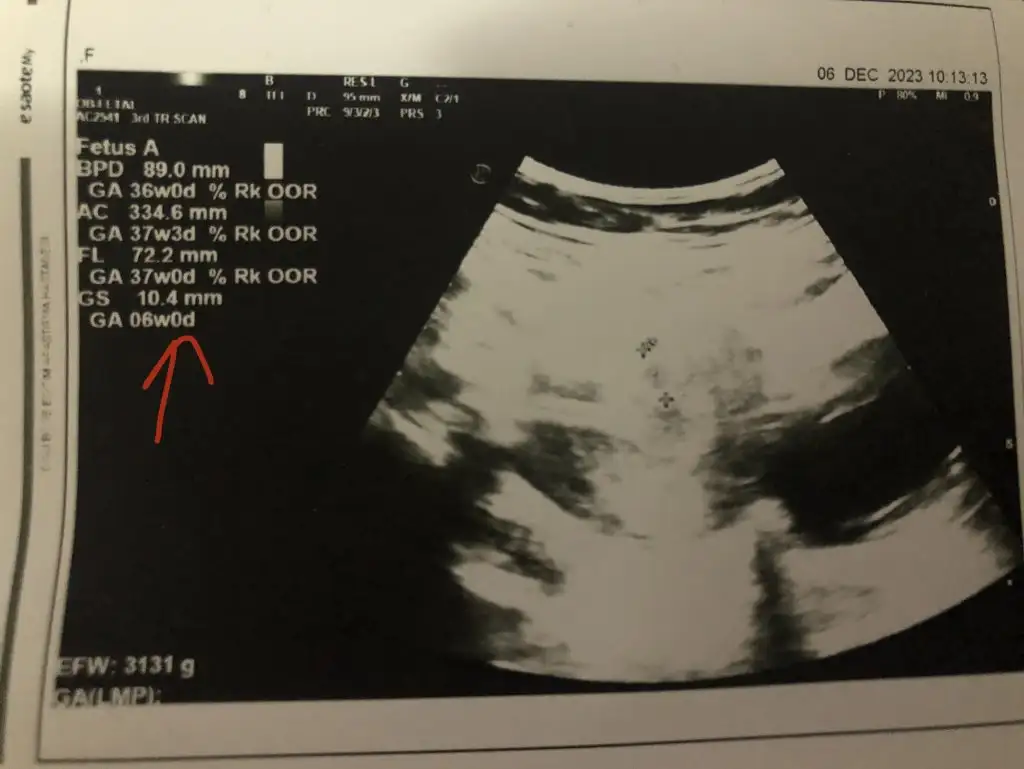

sag alt kosede yaziyor benimkinde hem haftasi hem boyutu

10 mm kese kaliba , sizinkinde baska sayilarda var emin olamadim o yuzden canim , kalp atisi duydunuz muEki Görüntüle 3348688

Burası oluyor sanırım 6 haftalık boyut hangisi oluyor ?